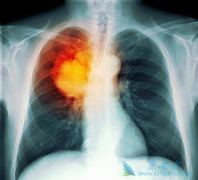

• 晚期肺癌患者吃EGFR-TKI吉非替尼出现肝毒性的原因是什么?

晚期肺癌患者吃EGFR-TKI吉非替尼出现肝毒性的原因是什么?

在目前已经公布的不同EGFR-TKI治疗晚期肺癌的III期临床研究中,药物性肝损伤(DILI)的发生率为5%-55.3%,≥3级的发生率为0.4%-26.3%。除阿法替尼外,多数 EGFR-TKI 主要通过肝脏酶系代谢。有研究认为EGFR-TKI的肝毒性与其活性代谢产物的代谢有关,而诱 ...